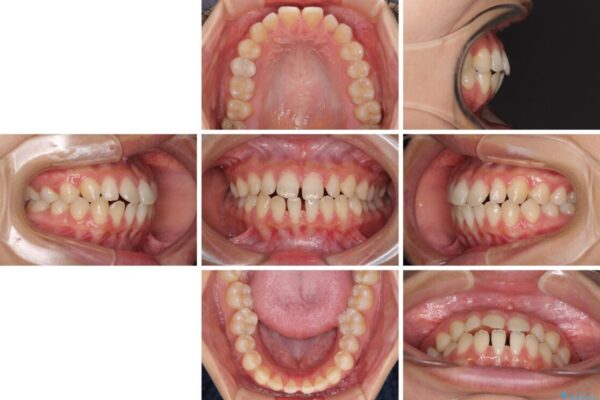

治療前

• 隙間だらけの歯列 インビザラインで改善 治療前画像